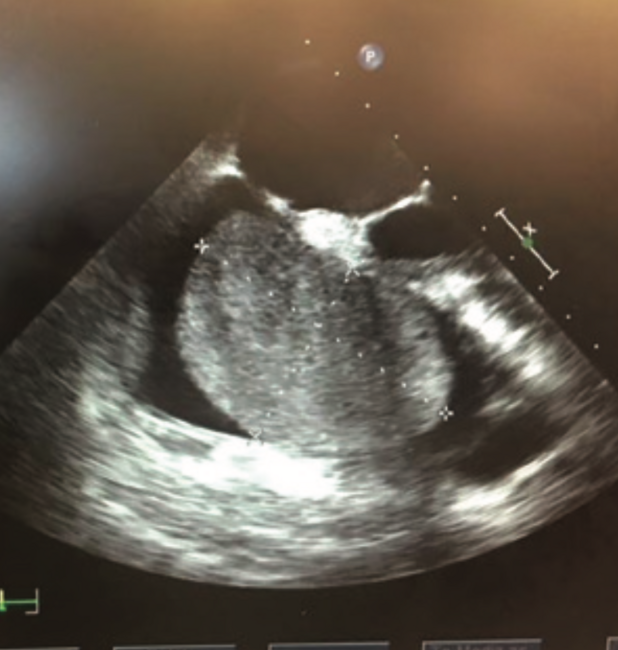

Cardiac myxomas are noncancerous primary tumors of the heart. The majority of cardiac myxomas are found in the left atrium and arise in the interatrial septum. Right atrial myxomas tend to be more solid and sessile, and have a wider attachment to the interatrial septum. Myxomas can lead to multiple complications resulting in obstruction, embolization, and constitutional symptoms. Right atrial myxomas are rare. We report the case of a massive round right atrial myxoma removed in a young male presenting with acute heart failure and embolism to the pulmonary vasculature. This 49-year-old male presented to an outpatient cardiology clinic with severe dyspnea on excretion and worsening pedal edema over a two-week period. Transesophageal echocardiogram demonstrated a 6 x 4 cm large mobile mass in the right atrium arising from the interatrial septum. He was found to be in acute congestive heart failure. A computed tomography angiogram of the chest demonstrated small pulmonary emboli in the right middle lobe, right lower lobe, and left lower lobe. He was subsequently anticoagulated and transferred to a tertiary care center. He underwent excision of the mass and the pathologic report was consistent with myxoma. Primary tumors of the heart are extremely rare. Right atrial myxomas are uncommon, and have not been previously reported to present with pulmonary embolism and congestive heart failure. In order to avoid complications from atrial myxoma, early diagnosis and surgical intervention is necessary. Clinicians should consider right atrial myxoma in their differential diagnosis of a patient presenting with pulmonary embolism and acute congestive heart failure.